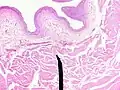

Microanatomy

When viewed under a microscope, the bladder can be seen to have an inner lining (called epithelium), three layers of muscle fibres, and an outer adventitia.[8]

The inner wall of the bladder is called urothelium, a type of transitional epithelium formed by three to six layers of cells; the cells may become more cuboidal or flatter depending on whether the bladder is empty or full.[8] Additionally, these are lined with a mucous membrane consisting of a surface glycocalyx that protects the cells beneath it from urine.[14] The epithelium lies on a thin basement membrane, and a lamina propria.[8] The mucosal lining also offers a urothelial barrier against the passing of infections.[15]

These layers are surrounded by three layers of muscle fibres arranged as an inner layer of fibres orientated longitudinally, a middle layer of circular fibres, and an outermost layer of longitudinal fibres; these form the detrusor muscle, which can be seen with the naked eye.[8]

The outside of the bladder is protected by a serous membrane called adventitia.[8][16]